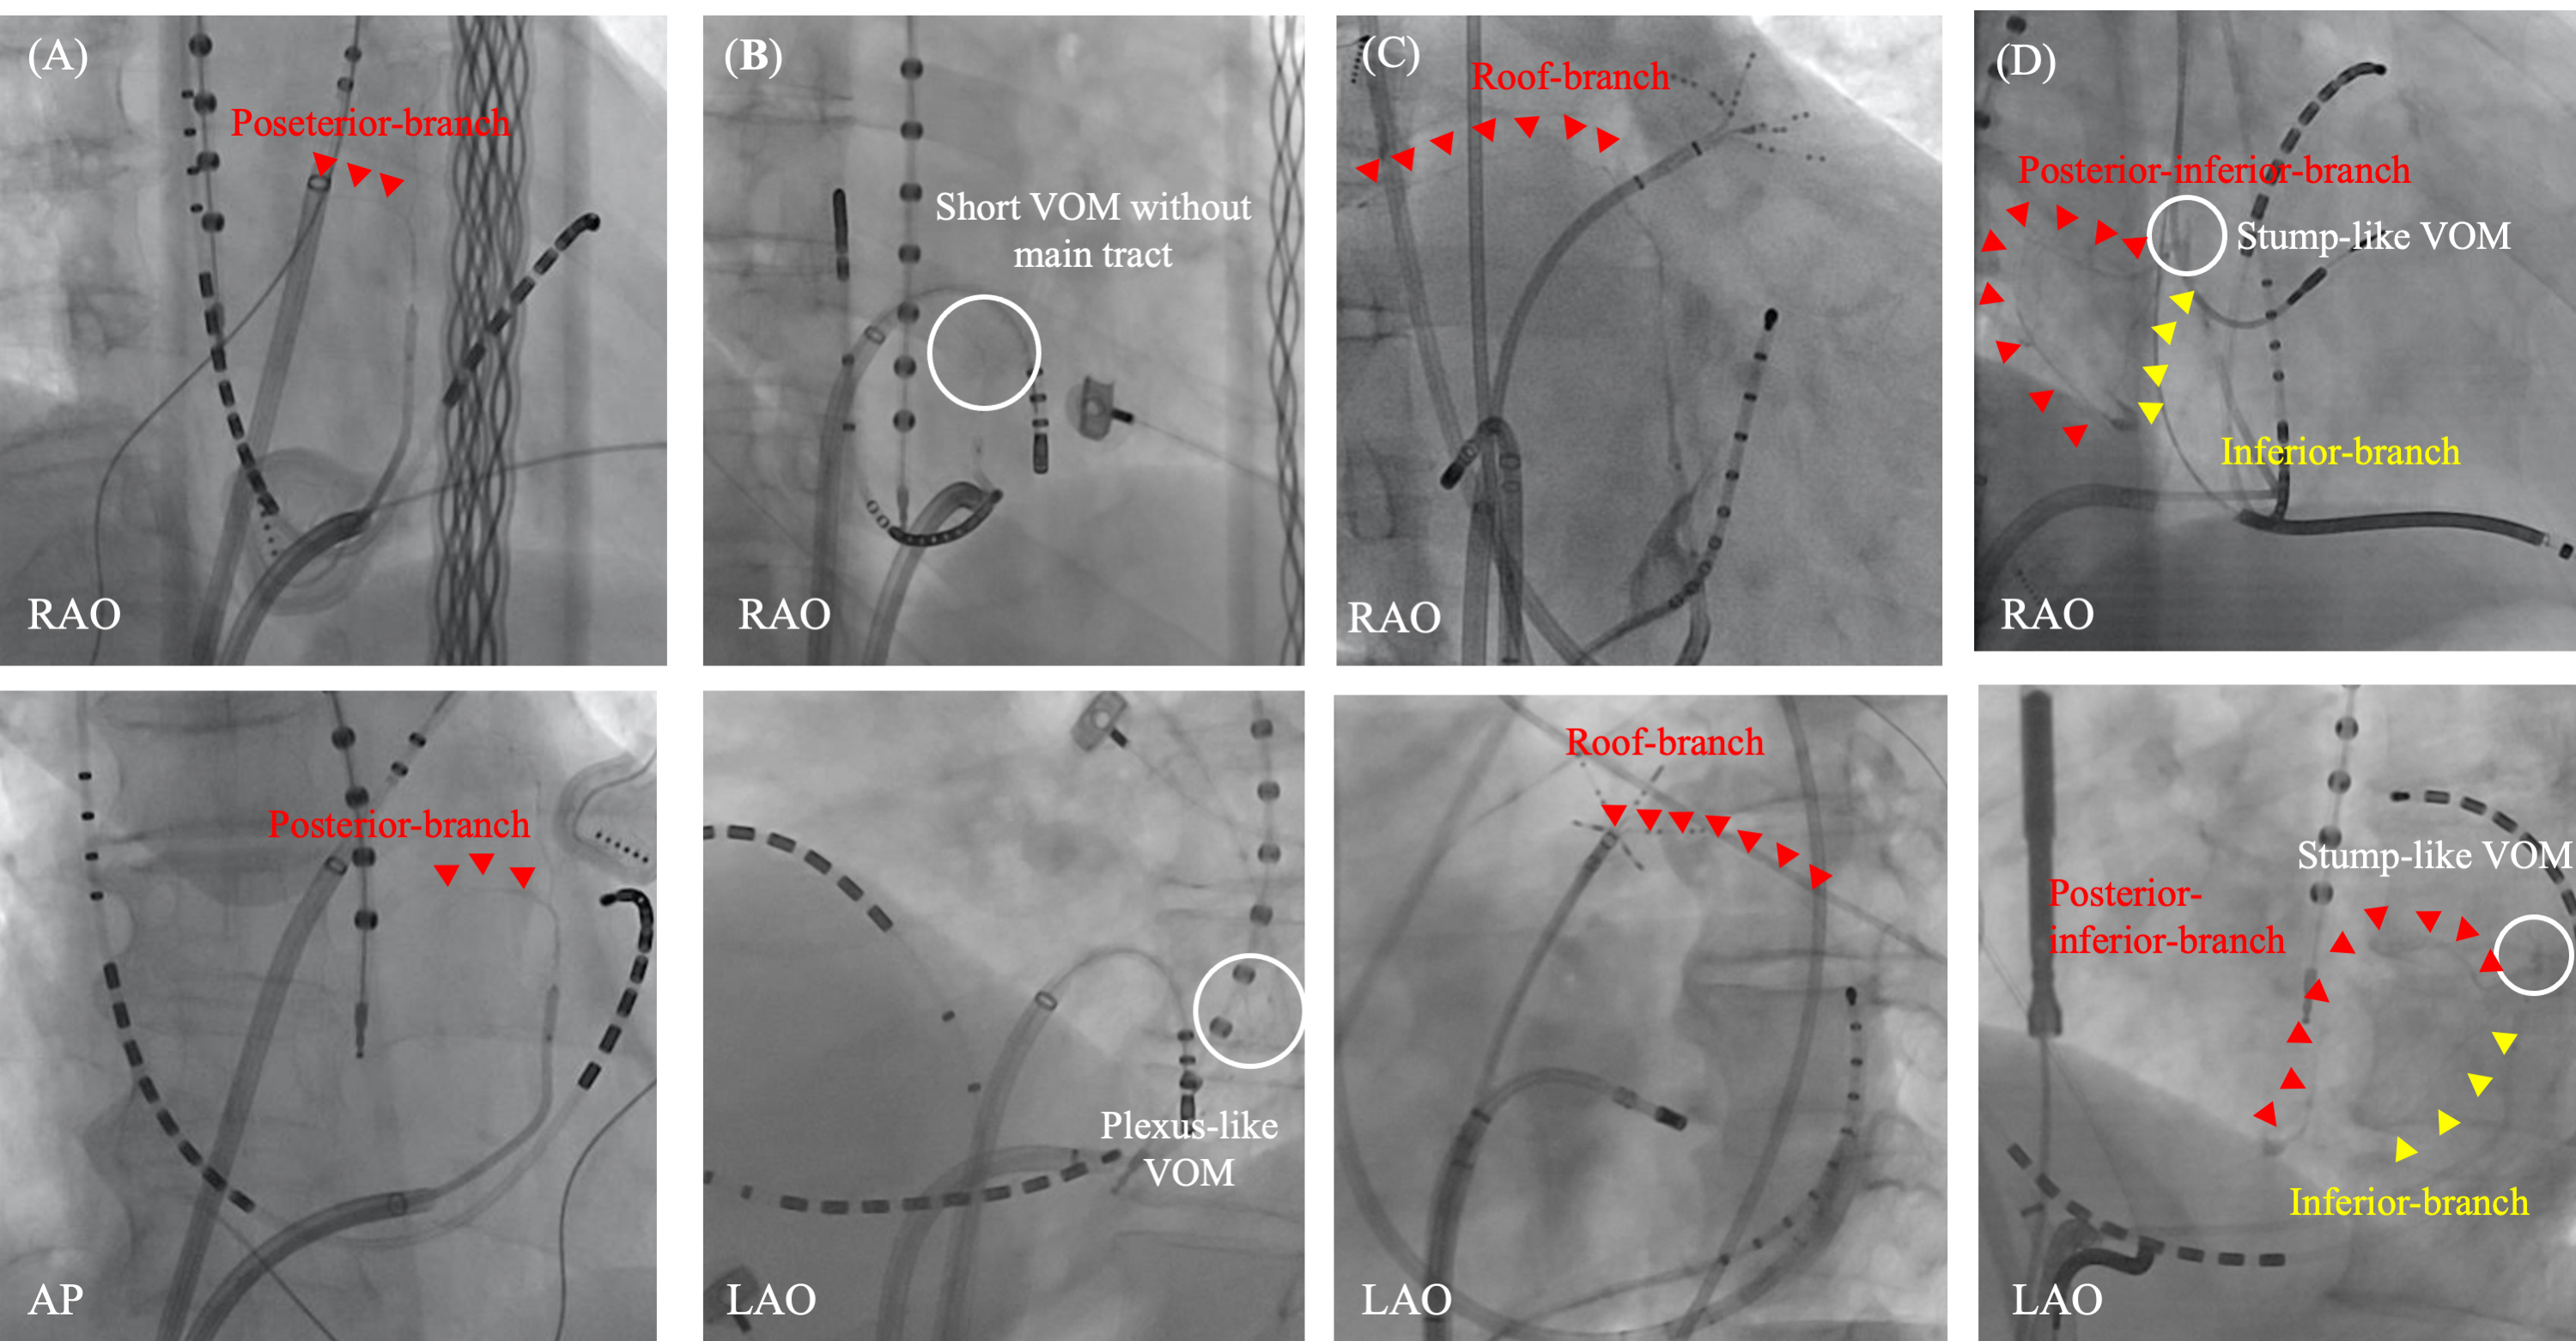

Fig. 6.Various distribution of VOM branches. Various distribution of VOM branches are observed. A posterior branch from the main VOM-tract (A). A plexus-like short-VOM without a main tract (B). A roof branch from the distal part of the main VOM-tract (C). Stump-like VOM with two branches from the VOM-ostium; one is a posterior-inferior branch and the other is inferior branch (D). AP, antero-posterior view; LAO, left anterior oblique view; RAO, right anterior oblique view; VOM, vein of Marshall.

Venous distribution is varied and abundant collaterals are observed in LA.

However, a constant pattern may be recognized and summarized in the report by

Valderrábano M et al. [16]. Beginning with the CS ostium, the LA

veins include: (1) a septal vein; (2) a second, inferior atrial vein; (3) the

VOM; (4) LAA veins; and (5) an anterior roof vein. Additionally, LA veins not

connected to the CS are observed, including (6) roof veins and posterior wall

veins commonly linked with (7) extracardiac collaterals. While the VOM is

consistently the most frequently found LA vein, identified as the vein arising at

the level of the valve of Vieussens (ostial to it), various venous distributions

and collaterals are still observed (Fig. 6). In our study, the distance from the

CS ostium to the VOM ostium was 4.25